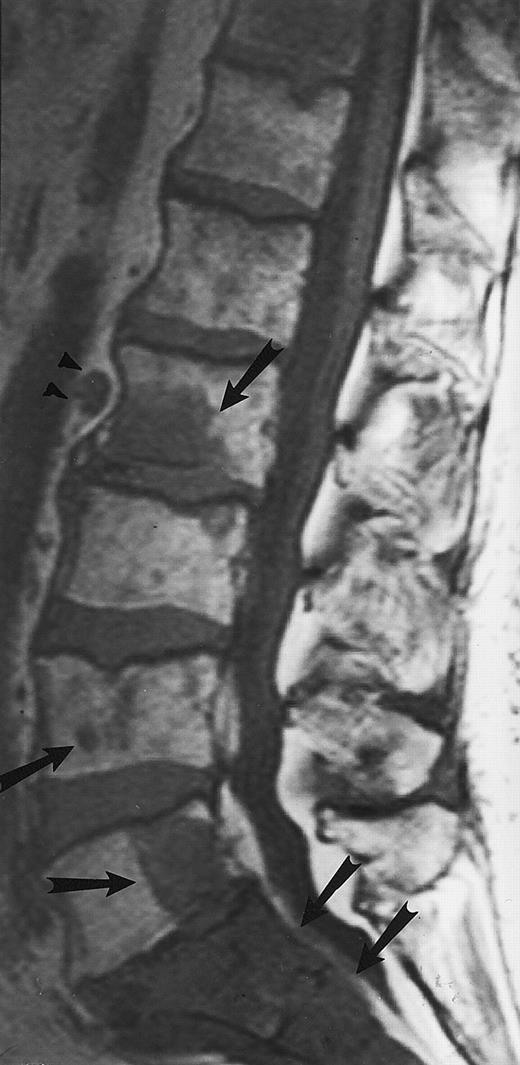

On T1-weighted MR images, lymphomatous involvement of the bone marrow is seen as diffuse, primarily heterogeneous replacement of the marrow and less frequently as focal marrow lesions (Figs 11 and 12).43,46 47 On T2-weighted images, the signal of the abnormal marrow increases, and on T1-weighted images after the intravenous administration of contrast, the abnormal marrow enhances. The MR patterns of lymphomatous involvement of the bone marrow may be indistinguishable from similar patterns in myeloma, leukemia, and other malignant or benign diseases of the bone marrow. MR imaging cannot differentiate between the different histologic subtypes of lymphoma.

An 8-year-old boy with Burkitt's lymphoma and diffuse marrow involvement. Fat-suppressed, T2-weighted fast spin echo (3000/96, TR/TE) sagittal MR image of the lumbar spine shows heterogeneous signal intensity of the bone marrow and epidural extension of tumor (arrowheads) at the level of L5 and L2, with apparent preservation of the vertebral cortex.

Lymphoma: multifocal bone marrow involvement. Sagittal T1-weighted (500/10, TR/TE) MR image of the lumbar spine shows multiple foci of bone marrow replacement (arrows). This appearance of lymphomatous involvement of the bone marrow is similar to bone metastases. Note extraosseous mass in the presacral space with apparent preservation of the bony cortex and small retroperitoneal lymph node at the level of L2 (arrowheads).

Its superior contrast resolution compared with CT makes MR imaging the modality of choice for the demonstration of soft tissue involvement. We have observed that extraosseous tumor in patients with lymphoma often occurs without obvious destruction of the cortical bone, reflecting the permeative nature of the tumor. MR images may show extensive involvement of the marrow and extraosseous soft tissues, with tumor “wrapped” around an apparently intact bony cortex48 (Figs 11 and 12). On bone radiographs and on CT, the involved bones may appear normal. This characteristic appearance of the extraosseous extent of lymphomatous involvement of the bone marrow is not pathognomonic for this disease and may be observed in other malignancies, particularly those of small cell origin. However, its presence may raise the possibility of lymphoma and direct the appropriate work-up. Caution should be taken to avoid misdiagnosing retroperitoneal lymphadenopathy for bone marrow involvement with extraosseous extension of tumor. Recently, Fenstermacher et al49 reported a 100% accuracy in the diagnosis of primary lymphoma of the bone versus osteosarcoma and Ewing sarcoma when no cortical destruction was detected in the area of bone marrow involvement and soft-tissue mass.